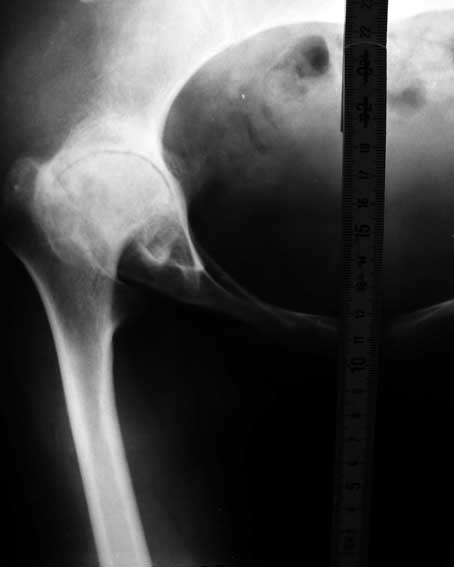

Перепробовал все имеющиеся виды шаблонов ножекпротезов - не подходят. На картинке линейка как масштаб - ширина 15мм.

Посмотрите на вертлужную впадину при ревматоидном артрите - вертлужная впадина не на месте, нет кости да и качество кости при ревматоидном артрите

плохое. Эндопротезирование в таком случае поможет на очень короткий срок.

Неизбежно и быстро возникнет расшатывание протеза. Повторные операции могут привести к состоянию значительно худшему чем сейчас. Я бы объяснил больной о возможных последствиях прежде чем оперировать.